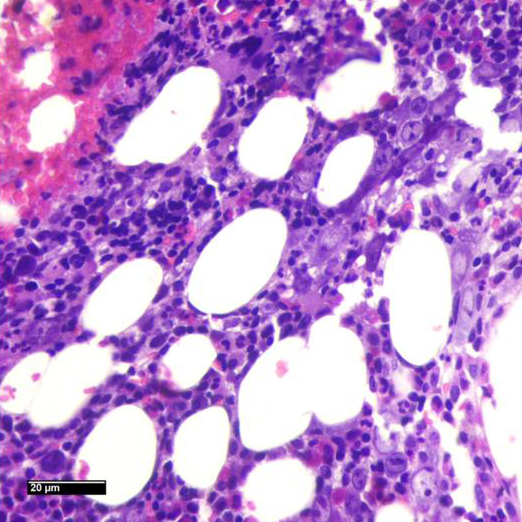

Se realiza punción de médula ósea.

Imágenes Microscopio

MÉDULA ÓSEA HIPERCELULAR CON CAMBIOS CITOPÁTICOS COMPATIBLES CON INFECCIÓN POR PARVOVIRUS

• La morfología típica muestra una médula ósea hipocelular, no como en este caso; pero las características citológicas de los eritroblastos, resaltadas en la coloración de Giemsa, que muestran macrocariosis e inclusiones nucleares; apoyadas por los hallazgos de la PCR confirman el diagnóstico.